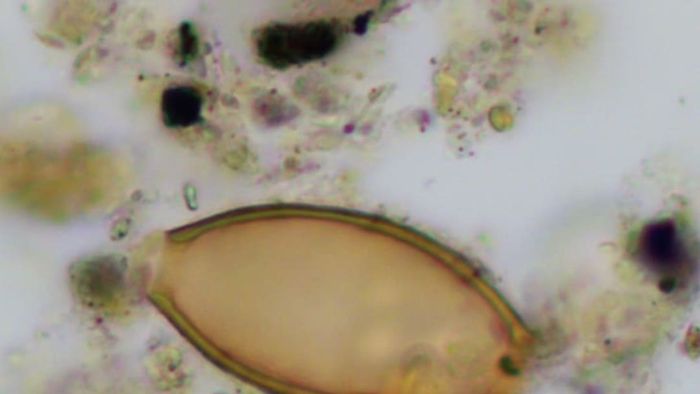

An egg of a roundworm | ElsevierApproximately 16 percent of the burials they examined revealed signs of parasites. In the ancient fecal samples, they discovered eggs from two distinct parasitic species. In the soil from Neolithic skeletons, they identified whipworm eggs, while the soil from Bronze Age remains contained roundworm eggs.

From this data, the researchers concluded that the Helmins strongyle mentioned by Hippocrates was likely what modern medicine refers to as roundworm. They further speculated that the Ascaris worm described by Hippocrates likely referred to two different parasites, which are known today as pinworm (not found in this study) and whipworm (shown below).